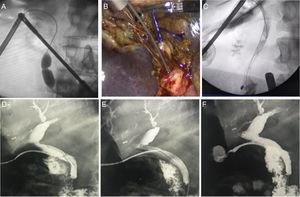

T-tube removal with guidewireThe T-tube is extracted 6–8 weeks after its placement and after having performed a fistulogram 10 days after surgery to confirm the absence of lithiasis and correct papillary drainage. The main complication of its removal is the rupture of the tract and posterior leakage or choleperitoneum. To avoid this, we insert a 0.035” hydrophilic guidewire (Roadrunner-Cook Medical®) through the T-tube to the duodenum under fluoroscopy, and then remove the tube, leaving the wire in the duodenum. We corroborate the integrity of the tract by performing a fistulogram through the cutaneous orifice. Then, the procedure is either concluded if there are no leaks, or a catheter is placed with the wire as a guide if there was contrast leakage due to rupture (Fig. 5D–F).